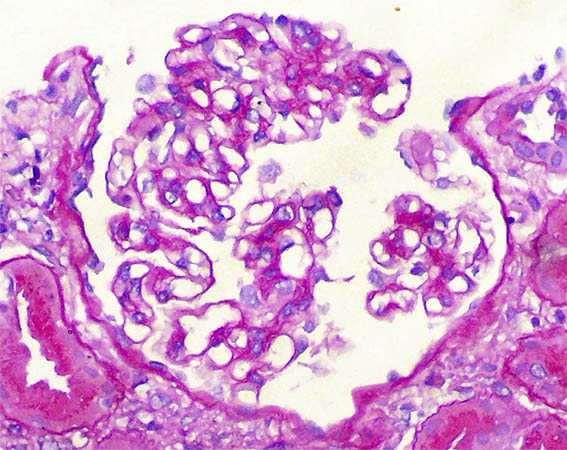

Figura 1. H&E, X200.

Figura 2. H&E, X200.